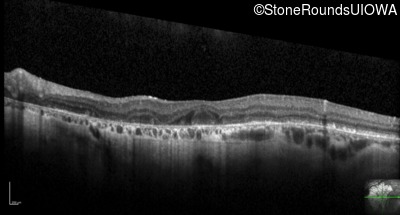

Optical Coherence Tomography - Right - 20/100 +1

Exemplar / OCT Stack

OCT Stack

Optical Coherence Tomography - Left - 20/200